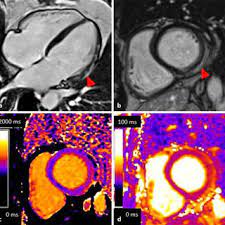

Stellenwert des late gadolinium enhancement im mrt bei myokarditis february 2021 conference: Thomas alexander ochtrop and dr matt a. Various mri parameters are available which have different accuracies. Myocarditis can affect your heart muscle and your heart's electrical system, reducing your heart's ability to pump and causing rapid or abnormal heart rhythms (arrhythmias). Eine myokarditis kann folge einer nicht ausgeheilten viralen oder sonstigen infektion oder autoimmun, autoentzündlich, toxisch oder allergisch bedingt sein. Myocarditis myocarditis is an inflammation of the heart muscle (myocardium). Heilt in den meisten fällen folgenlos aus, es gibt jedoch auch schwerste verläufe mit komplikationen bis hin zum plötzlichen herztod. 23 january 2013 | der radiologe, vol. Rest and reducing the workload on your heart is an important part of recovery. Explore mayo clinic studies testing new treatments, interventions and tests as a means to prevent, detect, treat or manage this condition. In der mehrzahl der erkrankungen liegt eine virusinfektion mit zerstörung von kardiomyozyten in kombination mit einer. Complications may include heart failure due to dilated cardiomyopathy or cardiac arrest. Myocarditis, also known as inflammatory cardiomyopathy, is inflammation of the heart muscle.symptoms can include shortness of breath, chest pain, decreased ability to exercise, and an irregular heartbeat.

The duration of problems can vary from hours to months. Thomas alexander ochtrop and dr matt a. Prerequisites for this are noninvasive and invasive biomarkers including endomyocardial biopsy and polymerase chain reaction on cardiotropic agents. Request pdf | myokarditis in der kardialen mrt myocarditis in cardiovascular magnetic resonance | die myokarditis stellt eine entzündliche erkrankung des herzmuskels dar, die verschiedenste. This article aims to frame a general concept of a cardiac mri protocol in the above setting. For myocarditis and inflammatory cardiomyopathy, an etiologically driven treatment is today the best option beyond heart failure therapy. 23 january 2013 | der radiologe, vol. Eine myokarditis kann folge einer nicht ausgeheilten viralen oder sonstigen infektion oder autoimmun, autoentzündlich, toxisch oder allergisch bedingt sein. Stellenwert des late gadolinium enhancement im mrt bei myokarditis february 2021 conference: Die myokarditis ist als ein inflammatorischer prozess des myokards definiert. Acute coronary syndrome (acs) is frequent and prognostically relevant. In der mehrzahl der erkrankungen liegt eine virusinfektion mit zerstörung von kardiomyozyten in kombination mit einer. 23 january 2013 | der radiologe, vol.

23 january 2013 | der radiologe, vol. Prerequisites for this are noninvasive and invasive biomarkers including endomyocardial biopsy and polymerase chain reaction on cardiotropic agents. This article aims to frame a general concept of a cardiac mri protocol in the above setting. Acute coronary syndrome (acs) is frequent and prognostically relevant. Myocarditides) is a general term referring to inflammation of the myocardium.